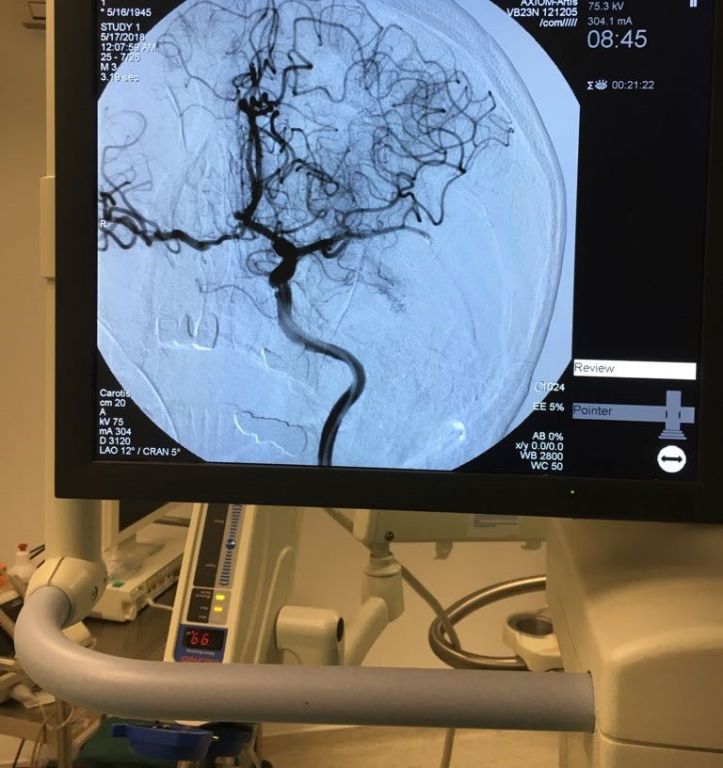

İzzet Baysal Eğitim ve Araştırma Hastanesinde yapılan işlemin aşamalarına ve tekniğine değinen Gürel; “Kanama gibi bazı riskler yoksa 1. aşama damardan pıhtı eritici ilaç vermek, ikinci aşama damarın içerisindeki pıhtıyı bir aletle çıkarmak. Hastanın hastaneye geldiği zaman ve ekip çok önemli. Hastanemizde ekip anlayışı içerisinde organizasyonumuzu kolaylıkla hızlıca yapabilmekteyiz.

Türkiye'de uygulanan 2 tip inme tedavisi şeklinin de hastanemizde uygulanabildiğini belirten Gürel; “İzzet baysal Eğitim ve Araştırma Hastanesi her iki hizmeti de vermeye başladı. Her yerde yapılamayan bu iki hizmeti ayrı ayrı ya da gerekli görüldüğünde aynı anda verebilecek kalitede son aşama hizmet vermekteyiz. Bu işlemlerle yatalak olacak hastayı hayata kazandırmış oluyoruz. Bu her hastada %100 başarı elde edeceğimizin kesin kararı değildir. Ancak bir ihtimal dahi olsa bu işlemi yapmaya değer. Ayrıca Bolu’da eğer biz bu hizmeti vermemiş olsaydık hastayı İstanbul ya da Ankara'ya götürdüğünüzde o bahsettiğimiz kritik zamanı yolda geçirmiş olacaktı ve işlemler için geç kalınacaktı.” dedi.